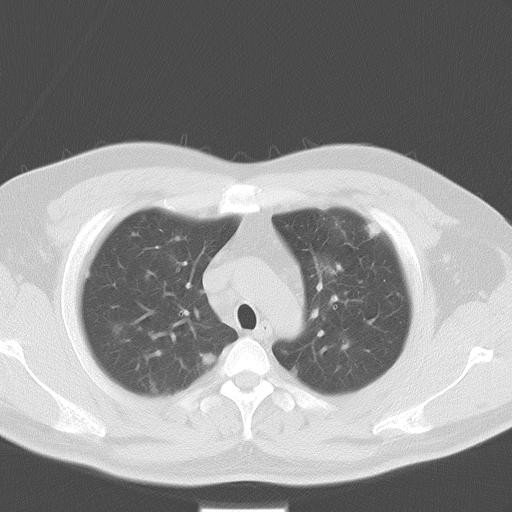

标题: CT13304:胸部多发结节影,少见,请会诊!!!! [打印本页]

标题: CT13304:胸部多发结节影,少见,请会诊!!!!

患者男性 35 主因发热咳嗽四天,血象不高,心肺听诊未见异常,无其它病史及传染病接触史。

两肺散在大小不等小结节影,下野较多,纵隔淋巴结增大。考虑:1、慢性血播性肺结核;2、霉菌病?3转移瘤待排。

两肺多发结节,部分病灶边缘不清,且示毛玻璃影。分布特点为沿血管支气管分布。

结合临床考虑;1,炎性肉芽肿性病变;霉菌?过敏性肺炎?2,韦格氏肉芽肿。3,转移瘤。